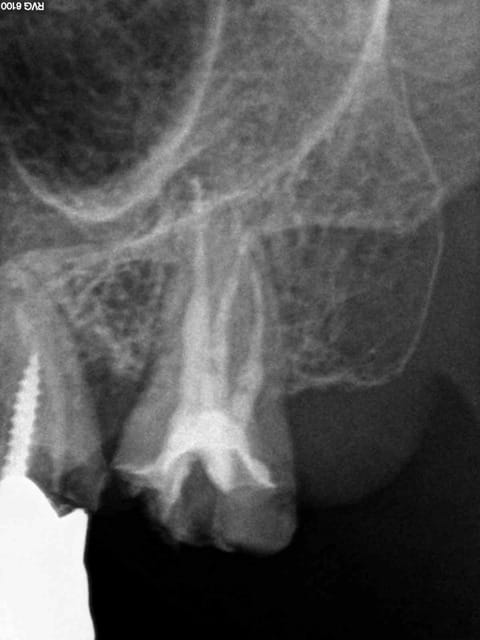

Ah, la France ses endos et soins conventionnels superbes classés au patrimoine de l'humanité.......

Encore un cas plus frais que le précédent, on innove cone sans pate cette fois ci ( ou la moitié du canal en 8 d'obturé. -)))

1 nhq0pn - Eugenol

2 l2h3ce - Eugenol

3 nnbzcw - Eugenol

4 wnkfxu - Eugenol